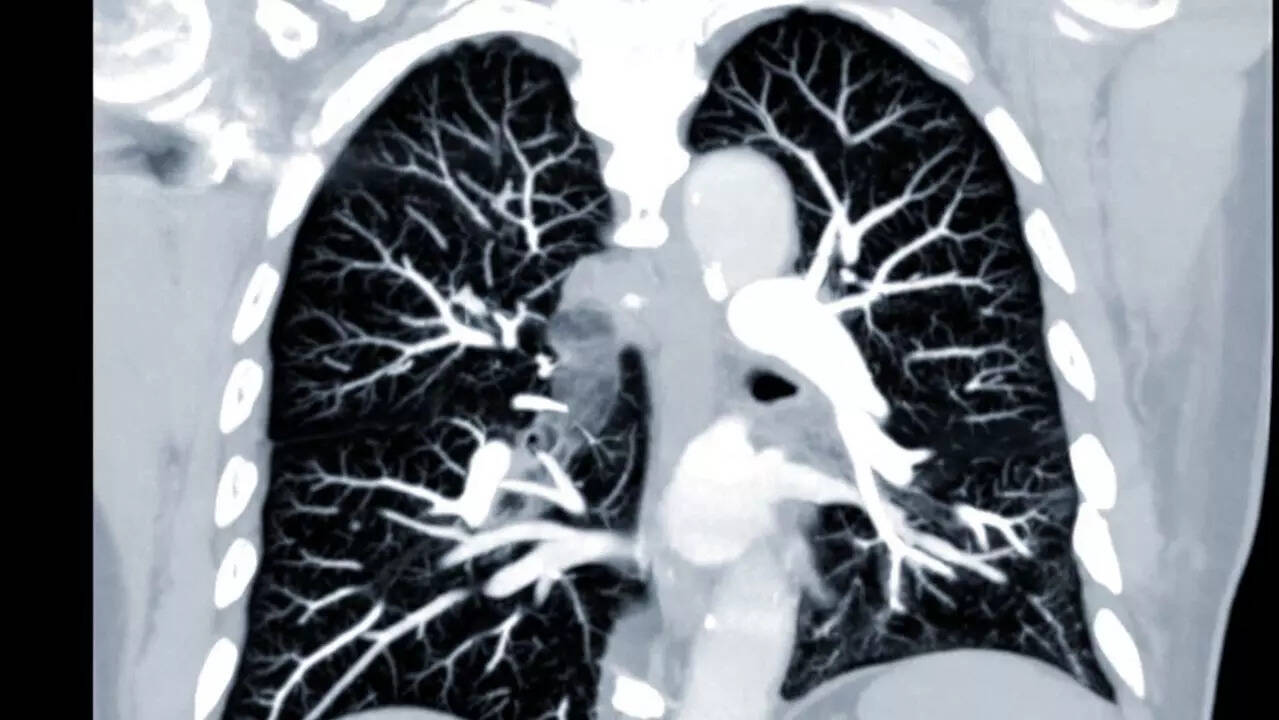

Pneumonia, a lung infection, can affect one of both lungs and may cause inflammation of air sacs which can lead to a fluid or pus build up. The symptoms may manifest as cough with phlegm or pus, fever, chills, and difficulty breathing. The disease can be caused by bacteria, viruses and fungi.

Kilmer was diagnosed with throat cancer in 2014 and his battle with the disease lasted for six years. While he was declared cancer-free, survivors may be at increased risk of certain diseases. Kilmer's treatment with radiotherapy and chemotherapy, and tracheostomy - which is done to create an artificial hole in the neck to support breathing, may have taken a toll on his health.

These treatments can affect immune system, making cancer survivors more prone to infections like pneumonia.

Certain health conditions can make you more susceptible to pneumonia. Chronic lung diseases such as COPD, bronchiectasis, or cystic fibrosis can make the lungs more vulnerable. Heart disease, diabetes and sickle cell disease can also increase your pneumonia risk.

A weakened immune system due to HIV/AIDs, an organ transplant, chemotherapy or long-term steroid use is a major culprit.